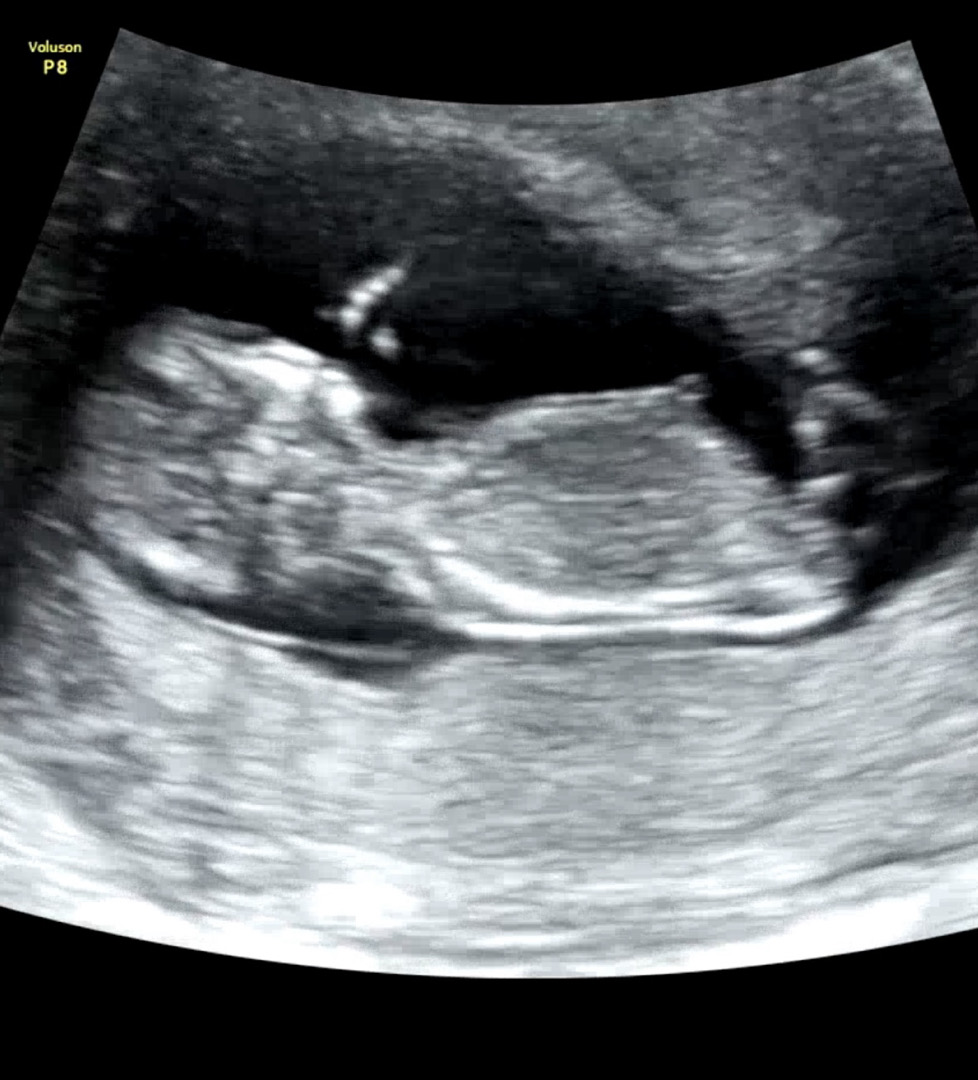

각도법 참견해주세요!!!

각도법 보이는 사진 맞을까요?